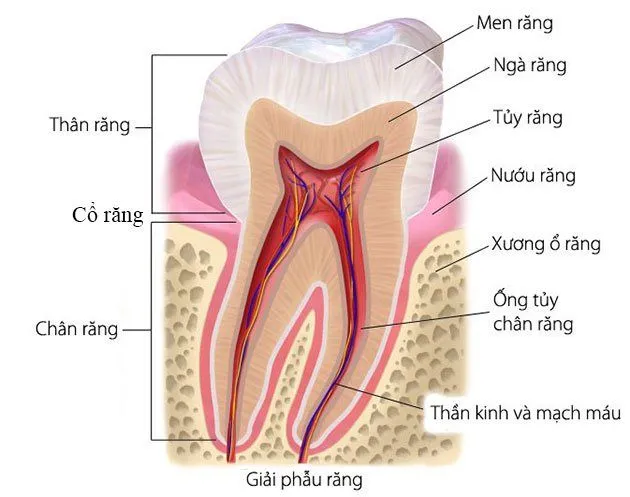

Các loại hàm răng là kiến thức cơ bản nhưng vô cùng quan trọng trong việc hiểu và chăm sóc sức khỏe răng miệng. Dù bạn đang

Câu hỏi “con nguoi co bao nhieu rang” luôn là thắc mắc phổ biến của nhiều người khi muốn hiểu rõ hơn về sức khỏe răng miệng.